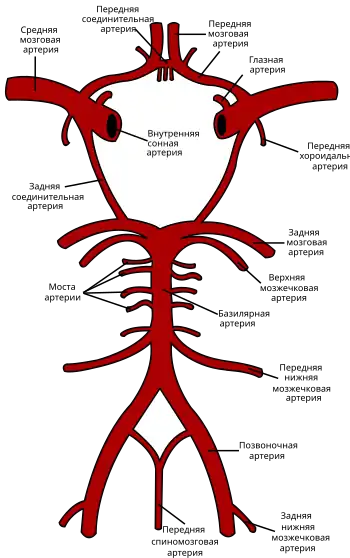

В соответствии с топической характеристикой очаговой неврологической симптоматики, по пораженному артериальному бассейну[12]:

- внутренняя сонная артерия;

- позвоночные, основная артерия и их ветви;

- средняя, передняя и задняя мозговые артерии.

Нарушения кровотока в бассейне внутренней сонной артерии (ВСА)

Закупорка ВСА может возникать в её начале (области бифуркации общей сонной артерии), каротидном сифоне и супраклиноидной части (чаще вследствие образования тромба на месте атеросклеротической бляшки) и протекать бессимптомно при достаточном коллатеральном кровообращении через артериальный круг большого мозга и другие анастомозы. При недостаточном коллатеральном кровообращении или в случаях артерио-артериальной эмболии возникают геми- или моноплегия, афазия и другие расстройства[16]:237. Развитие монокулярной слепоты на одной стороне и гемипареза на противоположной (окулопирамидный синдром) — характерно (патогномонично) для стеноза или закупорки ВСА[31].

Окклюзия передней ворсинчатой (хороидальной) артерии

Закупорка передней ворсинчатой артерии, отходящей от ВСА до её деления на среднюю и переднюю мозговые артерии обычно проявляется в виде контрлатерального (на противоположной стороне от окклюзии) гемипареза и гемигипалгезии вследствие поражения внутренней капсулы. Иногда отмечаются нарушения речи и зрительно-пространственной ориентации в результате ишемии таламуса, а также гемианопсии при поражении латерального коленчатого тела[16]:238.

Окклюзия передней мозговой артерии (ПМА)

Если закупорка возникла до отхождения передней соединительной артерии, то она может протекать бессимптомно вследствие коллатерального кровотока из противоположной ПМА[16]:238. Инфаркт при окклюзии ПМА проявляется контрлатеральным параличом нижней конечности и хватательным рефлексом. Характерны спастичность с непроизвольным сопротивлением пассивным движениям, абулия, абазия, персеверации и недержание мочи[31].

Закупорка возвратной артерии Гюбнера, ветви ПМА, приводит к поражению хвостатого ядра и передней ножки внутренней капсулы, что вызывает контрлатеральный парез руки, лица и языка, сопровождающийся дизартрией[16]:238.

Окклюзия средней мозговой артерии (СМА)

Для окклюзии СМА характерны контрлатеральные гемиплегия, гемигипестезия, гомонимная гемианопсия. Наблюдается контрлатеральный парез взора. При поражении доминантного полушария развивается афазия, при поражении недоминантного — апраксия, агнозия, асоматогнозия и анозогнозия.

При окклюзии отдельных ветвей СМА возникают парциальные синдромы: моторная афазия в сочетании с контрлатеральным парезом верхней конечности и лицевого нерва при поражении верхних ветвей; сенсорная афазия при поражении нижних ветвей[31].

Окклюзия задней мозговой артерии (ЗМА)

При окклюзии задней мозговой артерии возможно развитие одного из двух синдромов: сочетание гомонимной гемианопсии с амнезией, дислексией (без дисграфии) и лёгкого контрлатерального гемипареза с гемианестезией; либо сочетание поражения ипсилатерального глазодвигательного нерва с контрлатеральными непроизвольными движениями и контрлатеральной гемиплегией или атаксией[31].

Нарушение кровотока в базилярной и позвоночных артериях

При окклюзии ветвей базилярной артерии (в зависимости от уровня поражения) наблюдаются: ипсилатеральная атаксия; контрлатеральная гемиплегия и гемианестезия; ипсилатеральный парез взора с контрлатеральной гемиплегией; поражение ипсилатерального лицевого нерва; межъядерная офтальмоплегия; нистагм в сочетании с головокружением, тошнотой и рвотой; шум в ушах и потеря слуха; нёбная миоклония и осциллопсия.

При окклюзии ствола базилярной артерии или обеих позвоночных артерий наблюдается тетраплегия, двусторонний горизонтальный парез взора, кома или синдром изоляции («запертого человека», англ. locked-in state).

Поражение внутричерепного отдела позвоночной артерии или задненижней мозжечковой артерии сопровождается синдромами поражения продолговатого мозга. Наиболее часто наблюдается латеральный синдром продолговатого мозга: нистагм, головокружение, тошнота, рвота, дисфагия, охриплость голоса; ипсилатеральные нарушения чувствительности на лице, синдром Горнера и атаксия; контрлатеральное нарушение болевой и температурной чувствительности[31].